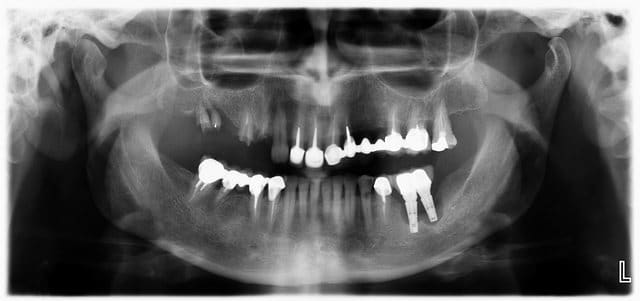

Reçu ce matin en urgence une patiente pour le descellement de son bridge sect 1... pano pour être sur que je ne pourrai pas le recoller et là... surprise sect 3 !!

Implants posés il y a 3 ans par un confrère, la patiente me dit avoir toujours été plus ou moins gênée par ces derniers, par période mais que son prat avait toujours remis en cause son hygiène et lui conseillait de bien passer les brossettes (version de patiente alors j'écoute en acquiescent mais j'essai de ne pas trop en tenir compte dans mon jugement)

En bouche, passage de brossette impossible entre les 2 implants, les cols sont à 1mm l'un de l'autre, poche paro plus profonde que ma sonde...

Que faire ? dépose l'implant distal me semble obligatoire... l'implant 36 aussi mais comment faire pour rompre l'intégration des dernières spires ?

tu déposes les implants curetage puis ROG soit biomat + membrane résorbable soit rien et membrane non résorbable renforcée...

dans 6 mois réévaluation et pose de 2 nouveaux implants...;-)

Sinon y'a pas un souci sur la demi-46 ?